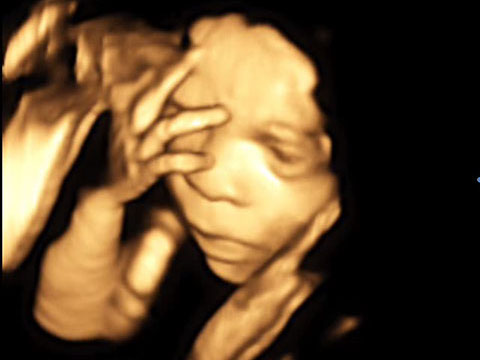

4D-Ultraschall

Der 4D-Ultraschall ist eine Methode der Ultraschall-Untersuchung, bei der das Ultraschallgerät ein dreidimensionales Bild des Untersuchungsobjekts in Echtzeit erzeugt.

Hier zeigt ein kleiner Film einen 4D-Ultraschall

Klicken, um den Film zu sehen